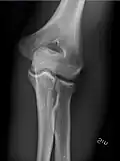

AP and lateral elbow X-ray

• Elbow - AP and Lateral. Radial head projections available on request